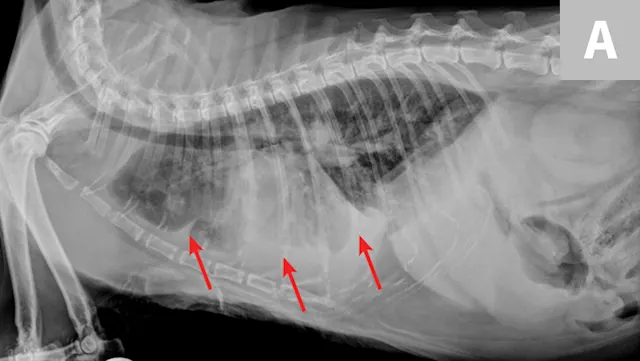

Radiographic evaluation is variable. Classic cranioventral distribution is less common in cats (Figure 3). A bronchial pattern is most common; however, bronchointerstitial, alveolar, and more structured pseudonodular patterns can occur.6,8 Occasionally, pulmonary abscesses may be appreciated and resemble pulmonary neoplasia (Figure 4).

FIGURE 3

Radiograph of bronchopneumonia with more classic cranioventral distribution (arrows). Other diseases, including CHF, have a similar distribution. Lack of this pattern does not rule out infection.